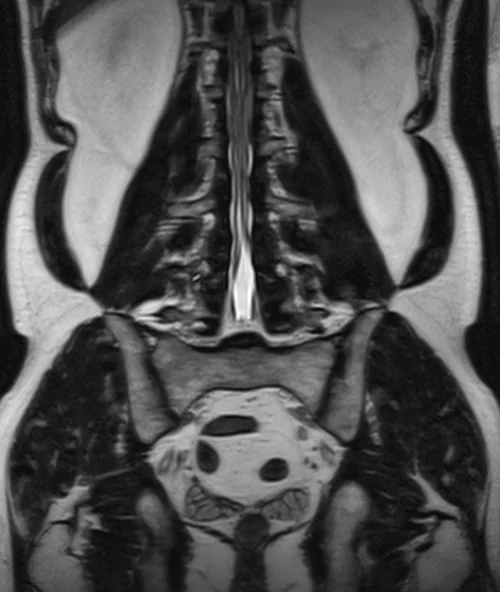

l plexus mri SPACE 3D coronal images